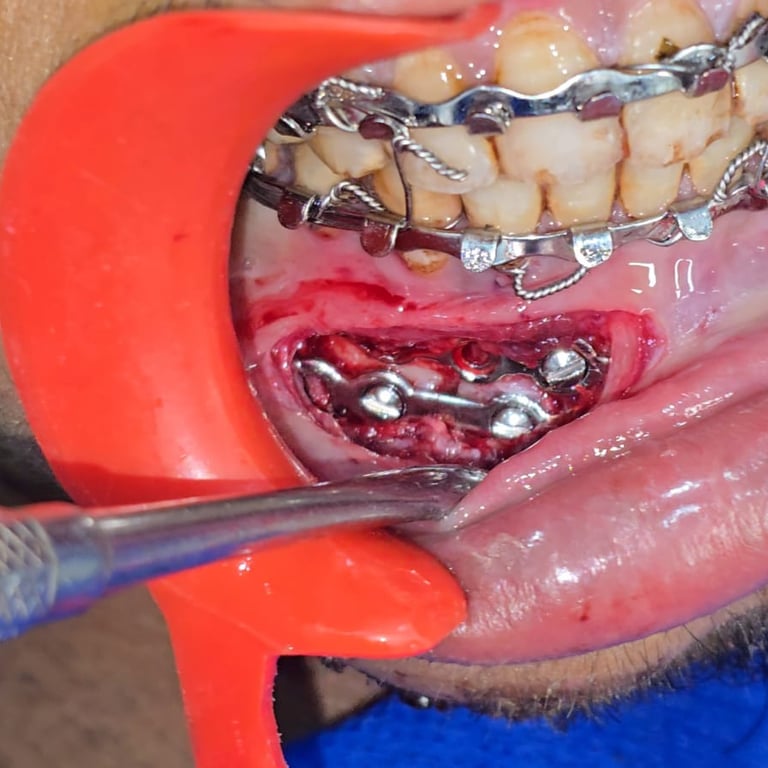

Surgery & Recovery

See how we treated a parasymphysis mandibular fracture in an 18-year-old male using IMF & plating. Scar-free recovery in just 15 days.